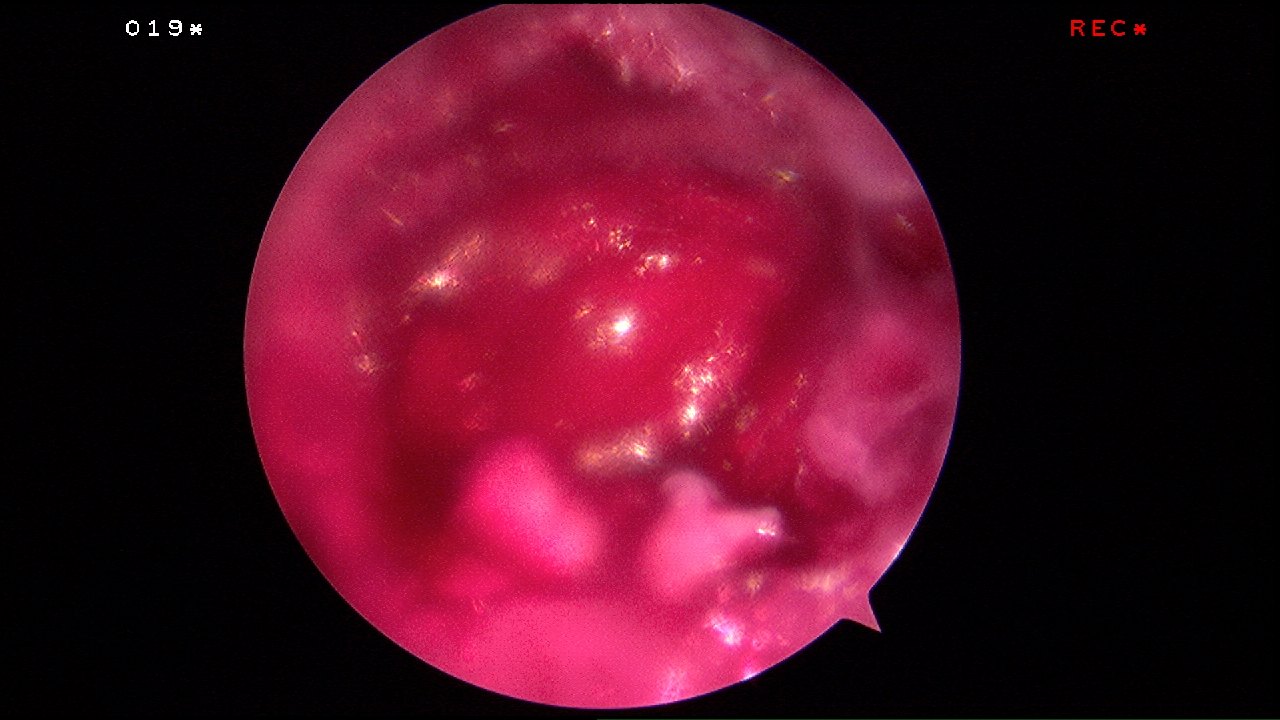

The tiny microfracture holes cause bleeding from the underlying bone marrow and it forms a so-called super-clot.

Over time, this super-clot will slowly form a type of repair cartilage called fibrocartilage.

Recent advances have allowed the surgeon to add a scaffold to cover up the cartilage defect after the microfracture has been done to keep the super-clot and the bone marrow cells within the defect.

This allows concentration of the available cells and super-clot to give the best healing potential.